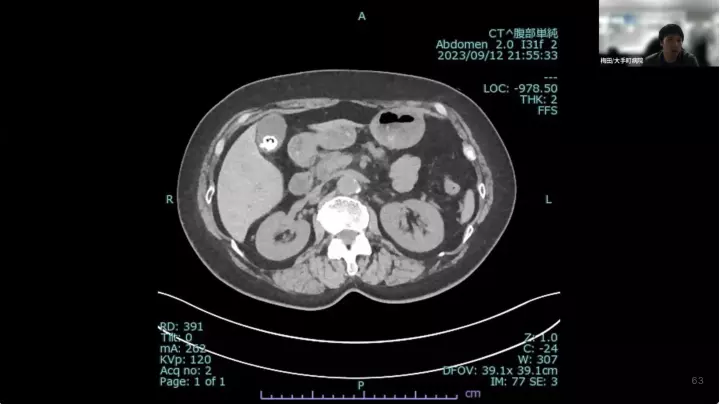

外科医目線の~急性胆嚢炎~治療編